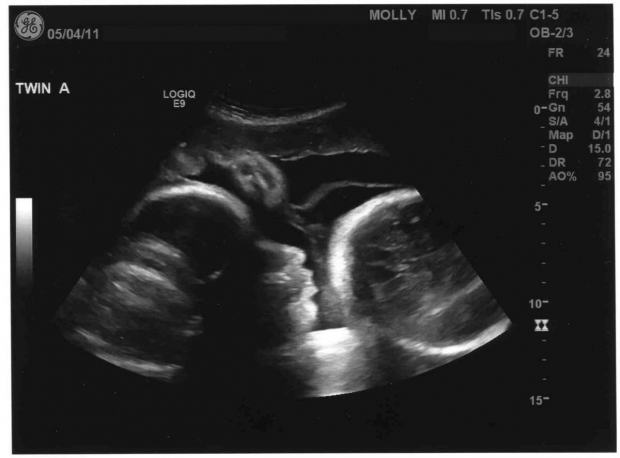

Фото плода на 36 неделе беременности (возраст плода 34 недели)

На 36-й неделе беременности рост здорового малыша достигает примерно 48 см, а его масса составляет около 2800 г. Средний размер головы в этот период равен 87,7 мм, диаметр грудной клетки – 91,8 мм, а окружность живота – 94,8 мм.

При нормальном ходе беременности ультразвуковое исследование на 36-й неделе обычно не проводится, за исключением определенных случаев, когда необходимо выяснить положение плода, оценить состояние кровотока, плаценты, а также количество и качество околоплодных вод.

На данном сроке плацента достигает второй степени зрелости, а ее толщина составляет около 36 мм. Если возникают подозрения на нарушения кровотока, врач может назначить допплерометрию артерий пуповины для более детального анализа.

Во время ультразвукового обследования плода основное внимание уделяется его весу, размерам и соответствию этим показателям сроку беременности. Если у матери узкий таз, а плод имеет крупные размеры, по итогам УЗИ может быть принято решение о проведении кесарева сечения. Также исследуется наличие обвития пуповиной различных частей тела плода и анализируется сама пуповина. Двойное или многократное тугое обвитие вокруг шеи ребенка является весомым основанием для выполнения кесарева сечения.

Фото УЗИ на 36 неделе беременности